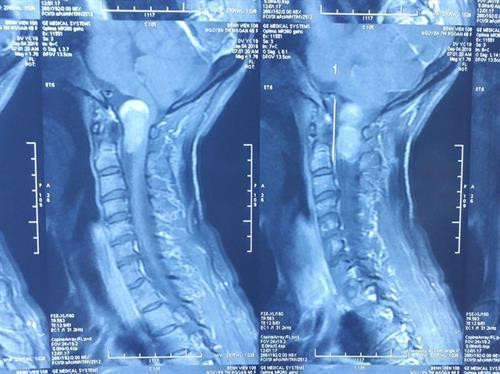

| Phim chụp Xquang ảnh khối u vùng chẩm cổ của bệnh nhân. Ảnh : baomoi.com |

Ngày 10/9, chị N. được gia đình đưa đến Bệnh viện Trung ương Quân đội 108 để khám. Tại đây, sau khi được làm các xét nghiệm, chụp Xquang, các bác sĩ chẩn đoán bệnh nhân bị u rễ thần kinh vùng chẩm cổ, khối u chèn ép tủy sống và hành tủy.